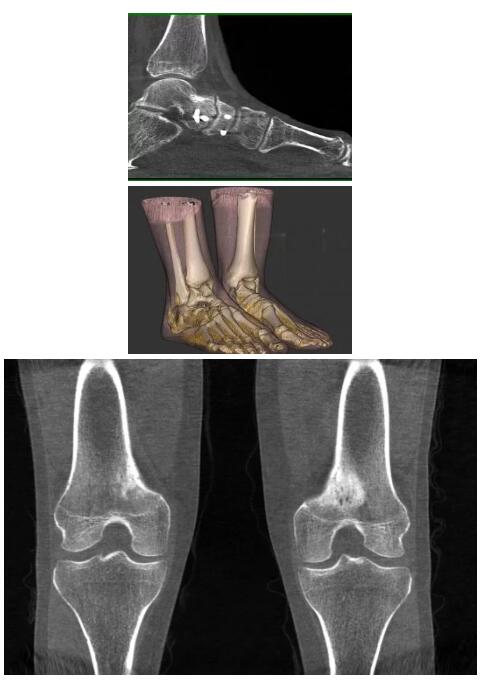

比如上面這款專用于足部和踝部掃查的CT成像系統(tǒng),患者在進(jìn)行CT掃查時(shí)只需要站在上面即可,雙腳站或者單腳站都可以,當(dāng)然,如果患者不是那么方便站著做完CT掃查,也可坐在上面。

這款CT掃查系統(tǒng)自帶屏蔽裝置,它的體積非常小,僅需要極小的空間即可,并不像常規(guī)CT那樣需要一間單獨(dú)的檢查室。此外,這種CT掃查的速度非常快,僅需30秒左右可以完成檢查,輻射劑量相對常規(guī)的CT要少許多,尤其適合醫(yī)院的骨科使用。

而患者站著做足部或者踝部做CT檢查還有個(gè)好處是,可以檢查患者在負(fù)重的情況下,骨關(guān)節(jié)的真實(shí)情況,而躺著做CT掃查時(shí)未必能看出來。負(fù)重CT掃查特別是對于受傷的運(yùn)動(dòng)員或者舞蹈員來說意義更大,能夠更準(zhǔn)確地評估傷情,幫助他們盡早復(fù)原。

以上介紹的CT均來自國外同一家公司,這些CT均配置了可視化軟件,可以進(jìn)行切片、3D重建以及大型CT附帶的所有典型的操作功能。

以下是這些“特立獨(dú)行”的CT所拍出來的圖像: